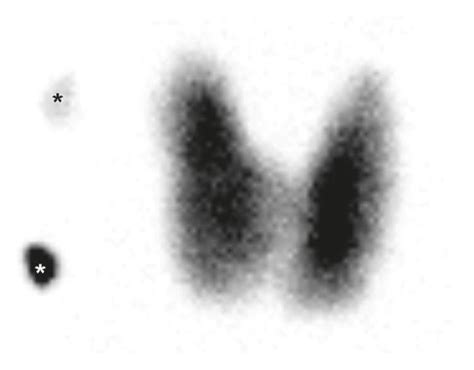

Alright, so why do doctors even bother with this radioiodine uptake test? Well, it’s a really valuable tool in their diagnostic toolbox, especially when they suspect something might be up with your thyroid. You see, just measuring your thyroid hormone levels in a blood test can sometimes give us a hint, but it doesn’t always tell the whole story. For instance, if your thyroid hormones are normal, but you’re still experiencing symptoms like unexplained weight loss, a racing heart, or feeling constantly anxious, a radioiodine uptake test can help pinpoint the cause. It’s particularly useful in diagnosing and managing hyperthyroidism, a condition where your thyroid produces too much hormone. Different causes of hyperthyroidism, like Graves’ disease or toxic nodular goiter, will show different patterns of radioiodine uptake. Graves’ disease, for example, typically shows a uniformly high uptake throughout the entire gland. On the other hand, toxic nodules will show uptake only in the specific nodule(s) that are overproducing hormones. This distinction is crucial because the treatment approaches for these different conditions can vary significantly. Furthermore, this test can help assess the severity of your thyroid condition and monitor how well you’re responding to treatment. It can also be used in conjunction with imaging techniques like a thyroid scan, which uses the same radioiodine to create a picture of your thyroid, showing its size, shape, and the location of any nodules or areas of abnormal activity. So, in essence, the radioiodine uptake test provides critical functional information that other tests might miss, guiding doctors toward the most effective treatment plan for you.

Okay, so you’ve had the test, and now you’re probably wondering, “What do these numbers mean ?” Interpreting your radioiodine uptake results is where your doctor really shines, but understanding the basics can help you feel more informed. The key number we look at is the percentage of the radioiodine dose that your thyroid has absorbed, usually measured at a specific time point (like 24 hours). Normal ranges can vary slightly between labs, but generally, a normal uptake percentage falls within a certain spectrum. If your uptake is higher than normal, it often suggests that your thyroid gland is working overtime, meaning it’s producing too much thyroid hormone. This is a hallmark of hyperthyroidism. Conditions like Graves’ disease, where your immune system mistakenly attacks your thyroid and causes it to overproduce hormones, typically result in a diffusely high radioiodine uptake. Another cause of high uptake is toxic multinodular goiter, where one or more nodules in the thyroid produce excess hormones. If your uptake is lower than normal, it can indicate that your thyroid isn’t producing enough thyroid hormone, a condition known as hypothyroidism. This might be seen in cases where the thyroid gland has been damaged, perhaps due to an autoimmune condition like Hashimoto’s thyroiditis, or if there’s a problem with the pituitary gland telling the thyroid to work harder. Sometimes, if you’ve recently had certain medical procedures or are taking specific medications that block iodine uptake, this can also lead to low results. It’s also important to consider the pattern of uptake if a scan was performed along with the uptake measurement. Are the nodules taking up the iodine, or is the whole gland active? This pattern provides even more clues. Remember, these results are always interpreted in the context of your symptoms, medical history, and other blood tests. Your doctor will sit down with you, explain what the numbers mean specifically for your situation, and discuss the next steps. Don’t hesitate to ask questions; understanding your results is the first step to managing your thyroid health effectively!

Let’s chat about what it means when your radioiodine uptake results come back higher than what’s considered typical. Generally, a high uptake signals that your thyroid gland is working extra hard, soaking up more iodine than it should. This is a classic sign of hyperthyroidism, a condition where your thyroid produces too much thyroid hormone. One of the most common culprits behind a high uptake is Graves’ disease . In Graves’ disease, your immune system gets a bit confused and starts producing antibodies that actually stimulate your thyroid to grow and pump out excess hormones. This usually results in a widespread, high uptake throughout the entire thyroid gland. Another reason for elevated radioiodine uptake is toxic nodular goiter . Here, one or more lumps, called nodules, form within your thyroid gland. These nodules can become ‘hot,’ meaning they are overactive and produce thyroid hormones independently of the rest of the gland. In this case, the uptake might be high overall, but the scan could show that the radioactivity is concentrated in specific nodules rather than spread evenly. Sometimes, even a simple goiter (an enlarged thyroid) without specific nodules can show increased uptake if the gland is trying to compensate for something. It’s really important to know why your uptake is high, because the treatment for Graves’ disease is different from the treatment for toxic nodular goiter. Your doctor will use these uptake results, along with other tests like thyroid antibody levels and possibly a thyroid scan, to figure out the specific cause of your hyperthyroidism. This precise diagnosis is key to getting you the right treatment to bring your thyroid hormone levels back to normal and help you feel like yourself again. High uptake is a signal that your thyroid needs attention, and with the right diagnosis, you can get back on track!